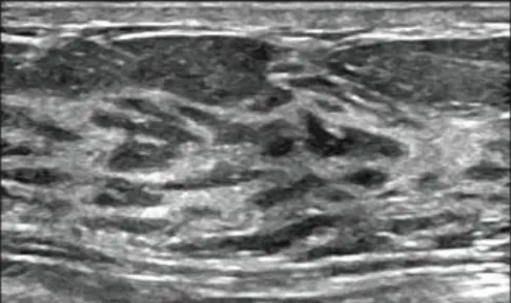

目前检查乳腺增生最简便的方法:乳腺超声检查。